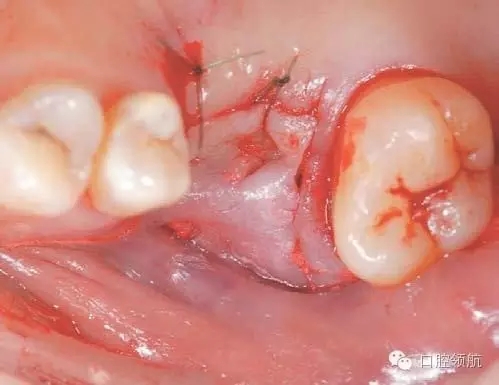

完全去除拔牙窩內的肉芽組織,造成上頜竇底的青枝骨折(圖4),植入骨替代材料行上頜竇底提升術。

圖4 確認上頜竇黏膜增厚消失,而且OMC的換氣和排泄功能已改善后,實施經牙槽嵴頂入路的上頜竇底提升術。按照常規(guī),造成上頜竇底的青枝骨折,提升上頜竇底。